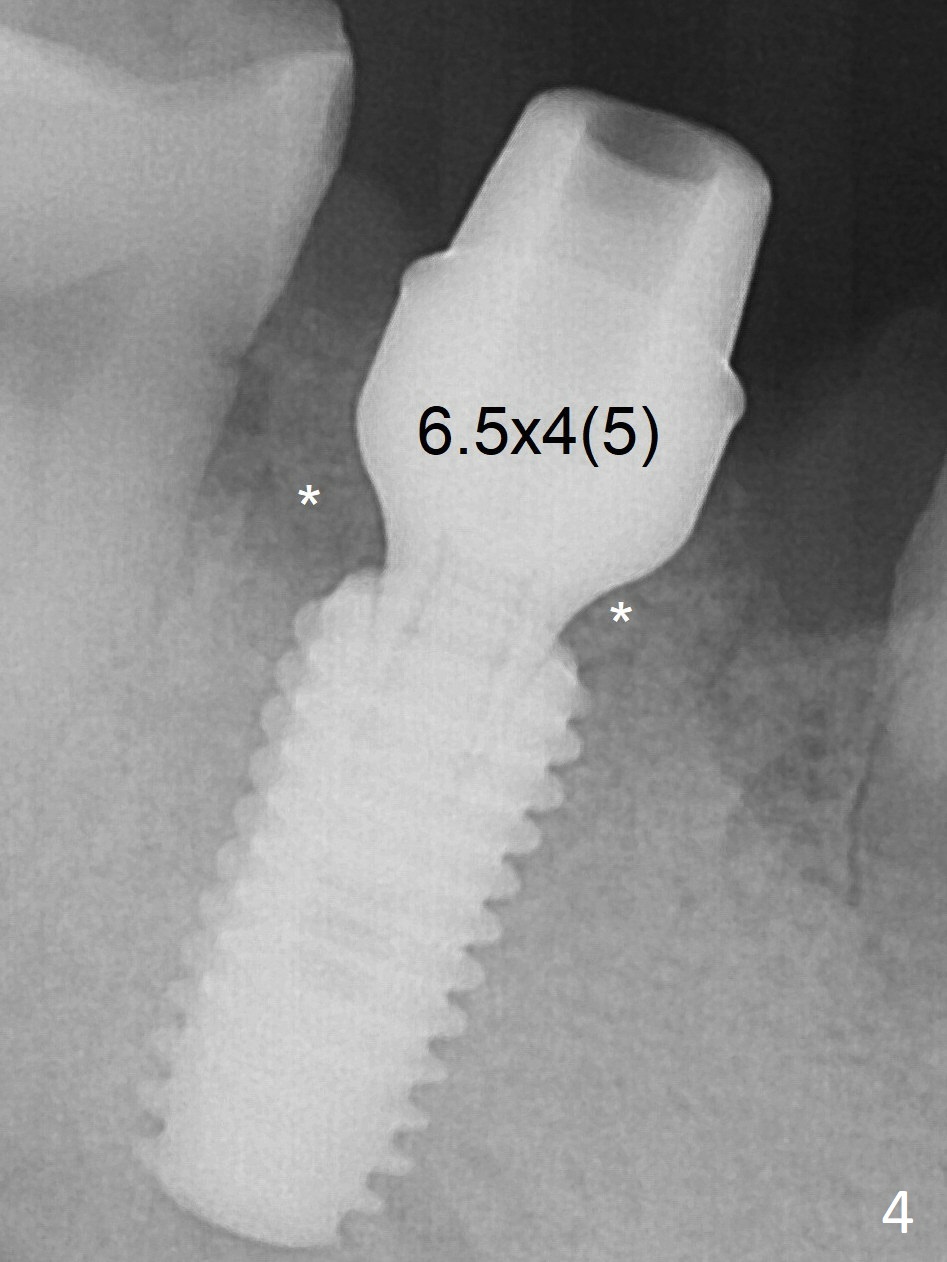

Following 4.8 mm drill, a 5.5x11.5 mm implant is placed initially (Fig.3) with an apical space (*) and clearance between the osteotomy and the Inferior Alveolar Canal (red dashed line).  The implant is placed deeper with placement of a 6.5x4(5) mm abutment and bone graft (*, Fig.4).  There is no bone loss 3.5 months postop (Fig.8).  The abutment margin is lowered by prep before impression.  In fact the abutment has not been seated completely since its placement (Fig.4,5,8).